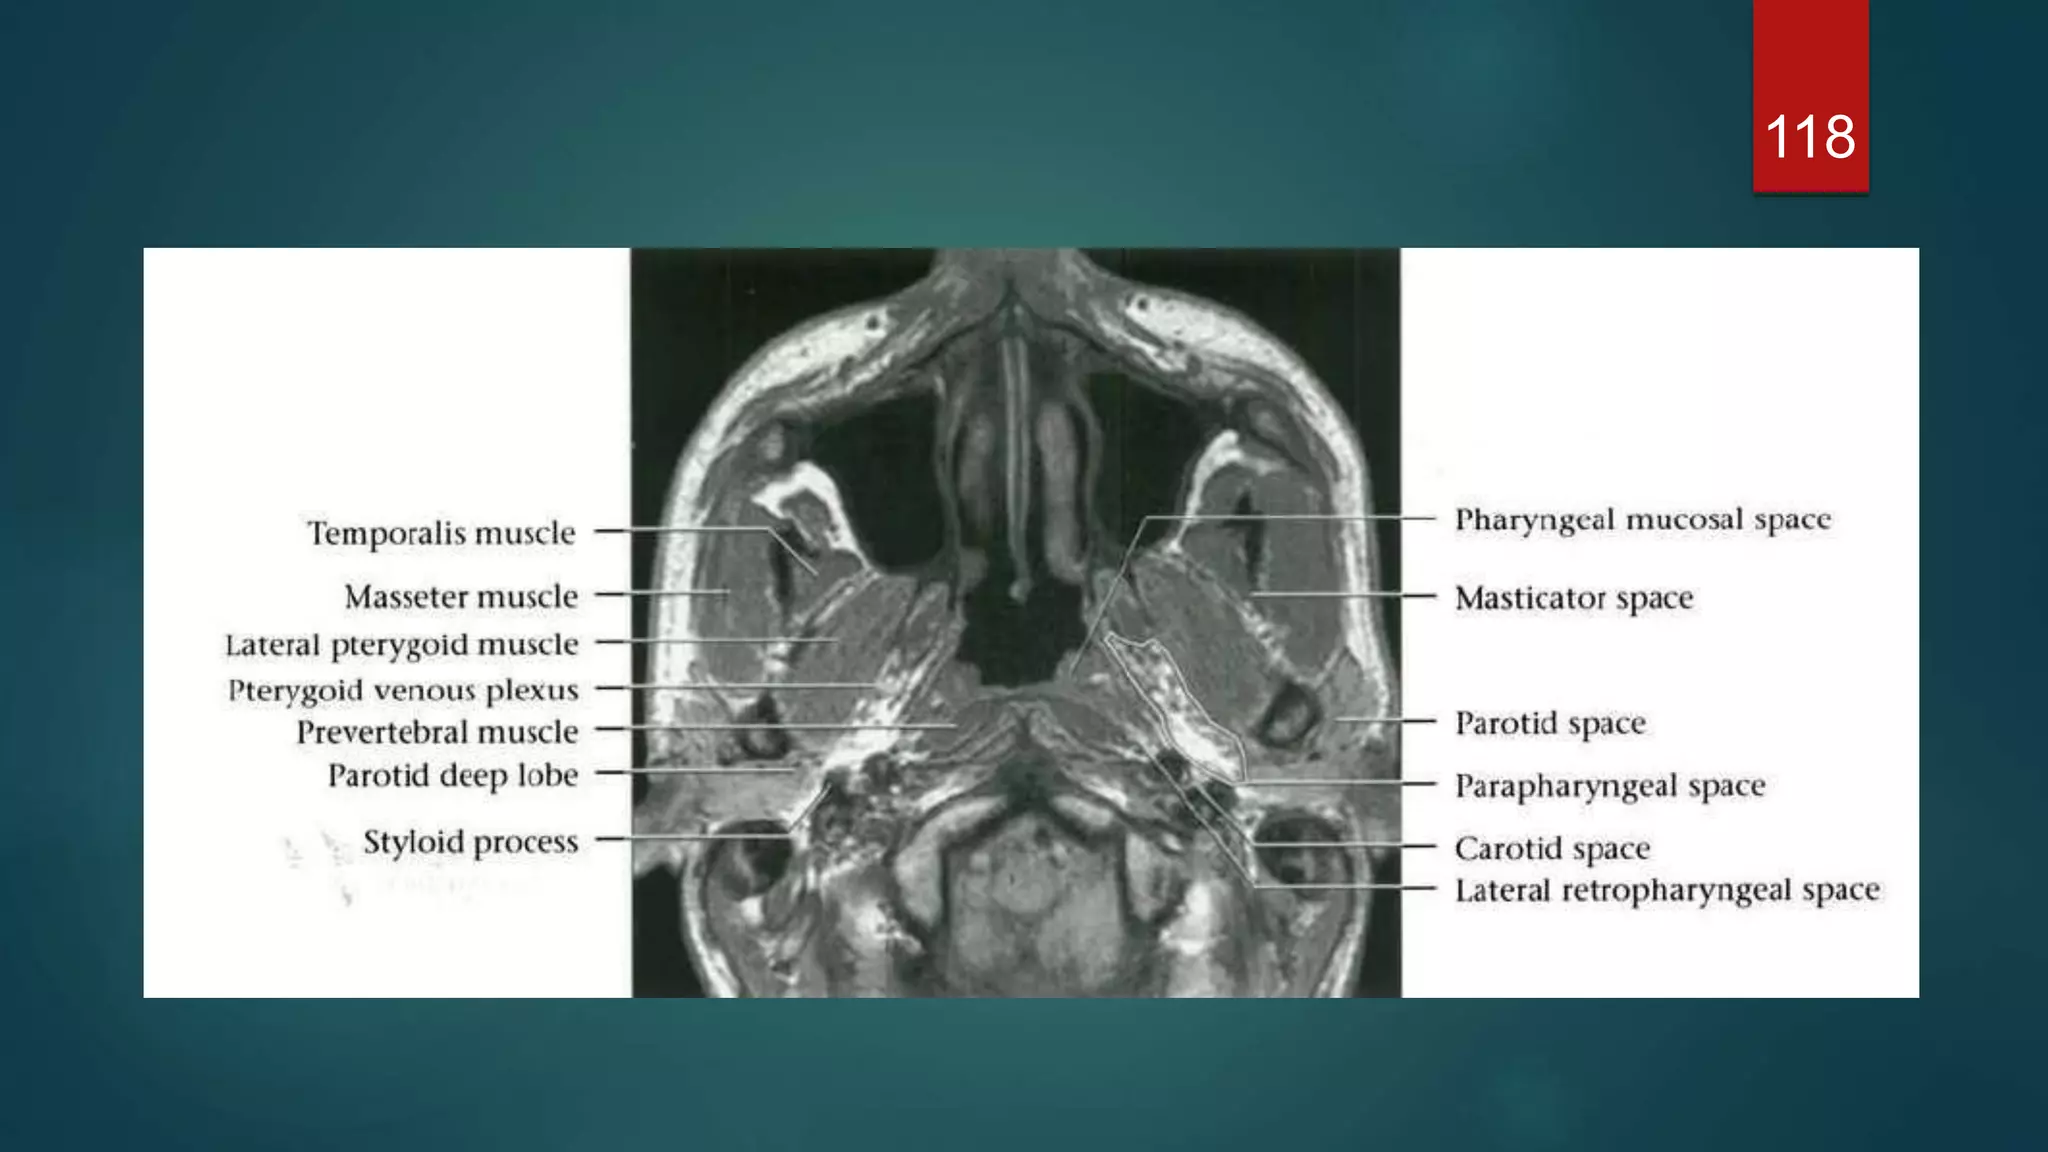

MRI

118